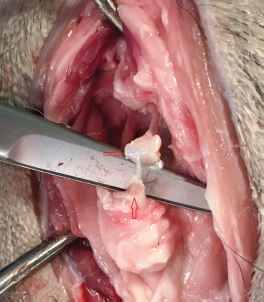

One shoulder experienced iatrogenic damage during the bicipital transection; partway through the procedure, the first researcher realized the needle was angled cranially rather than perpendicular to the long axis of the humerus. The needle angle was corrected and the procedure was completed successfully, but upon dissection it was determined that the cartilage surface of the humeral head had multiple full thickness lacerations (Fig. 7). Additionally, there was a 2–3 mm laceration of the medial aspect of the supraspinatus tendon (Fig. 8). Superficial scoring of the cartilage of the bicipital groove by the tip of the needle was evident in all shoulders at the level of the transection.

Fig. 8. Iatrogenic laceration of the supraspinatus tendon (red arrow).